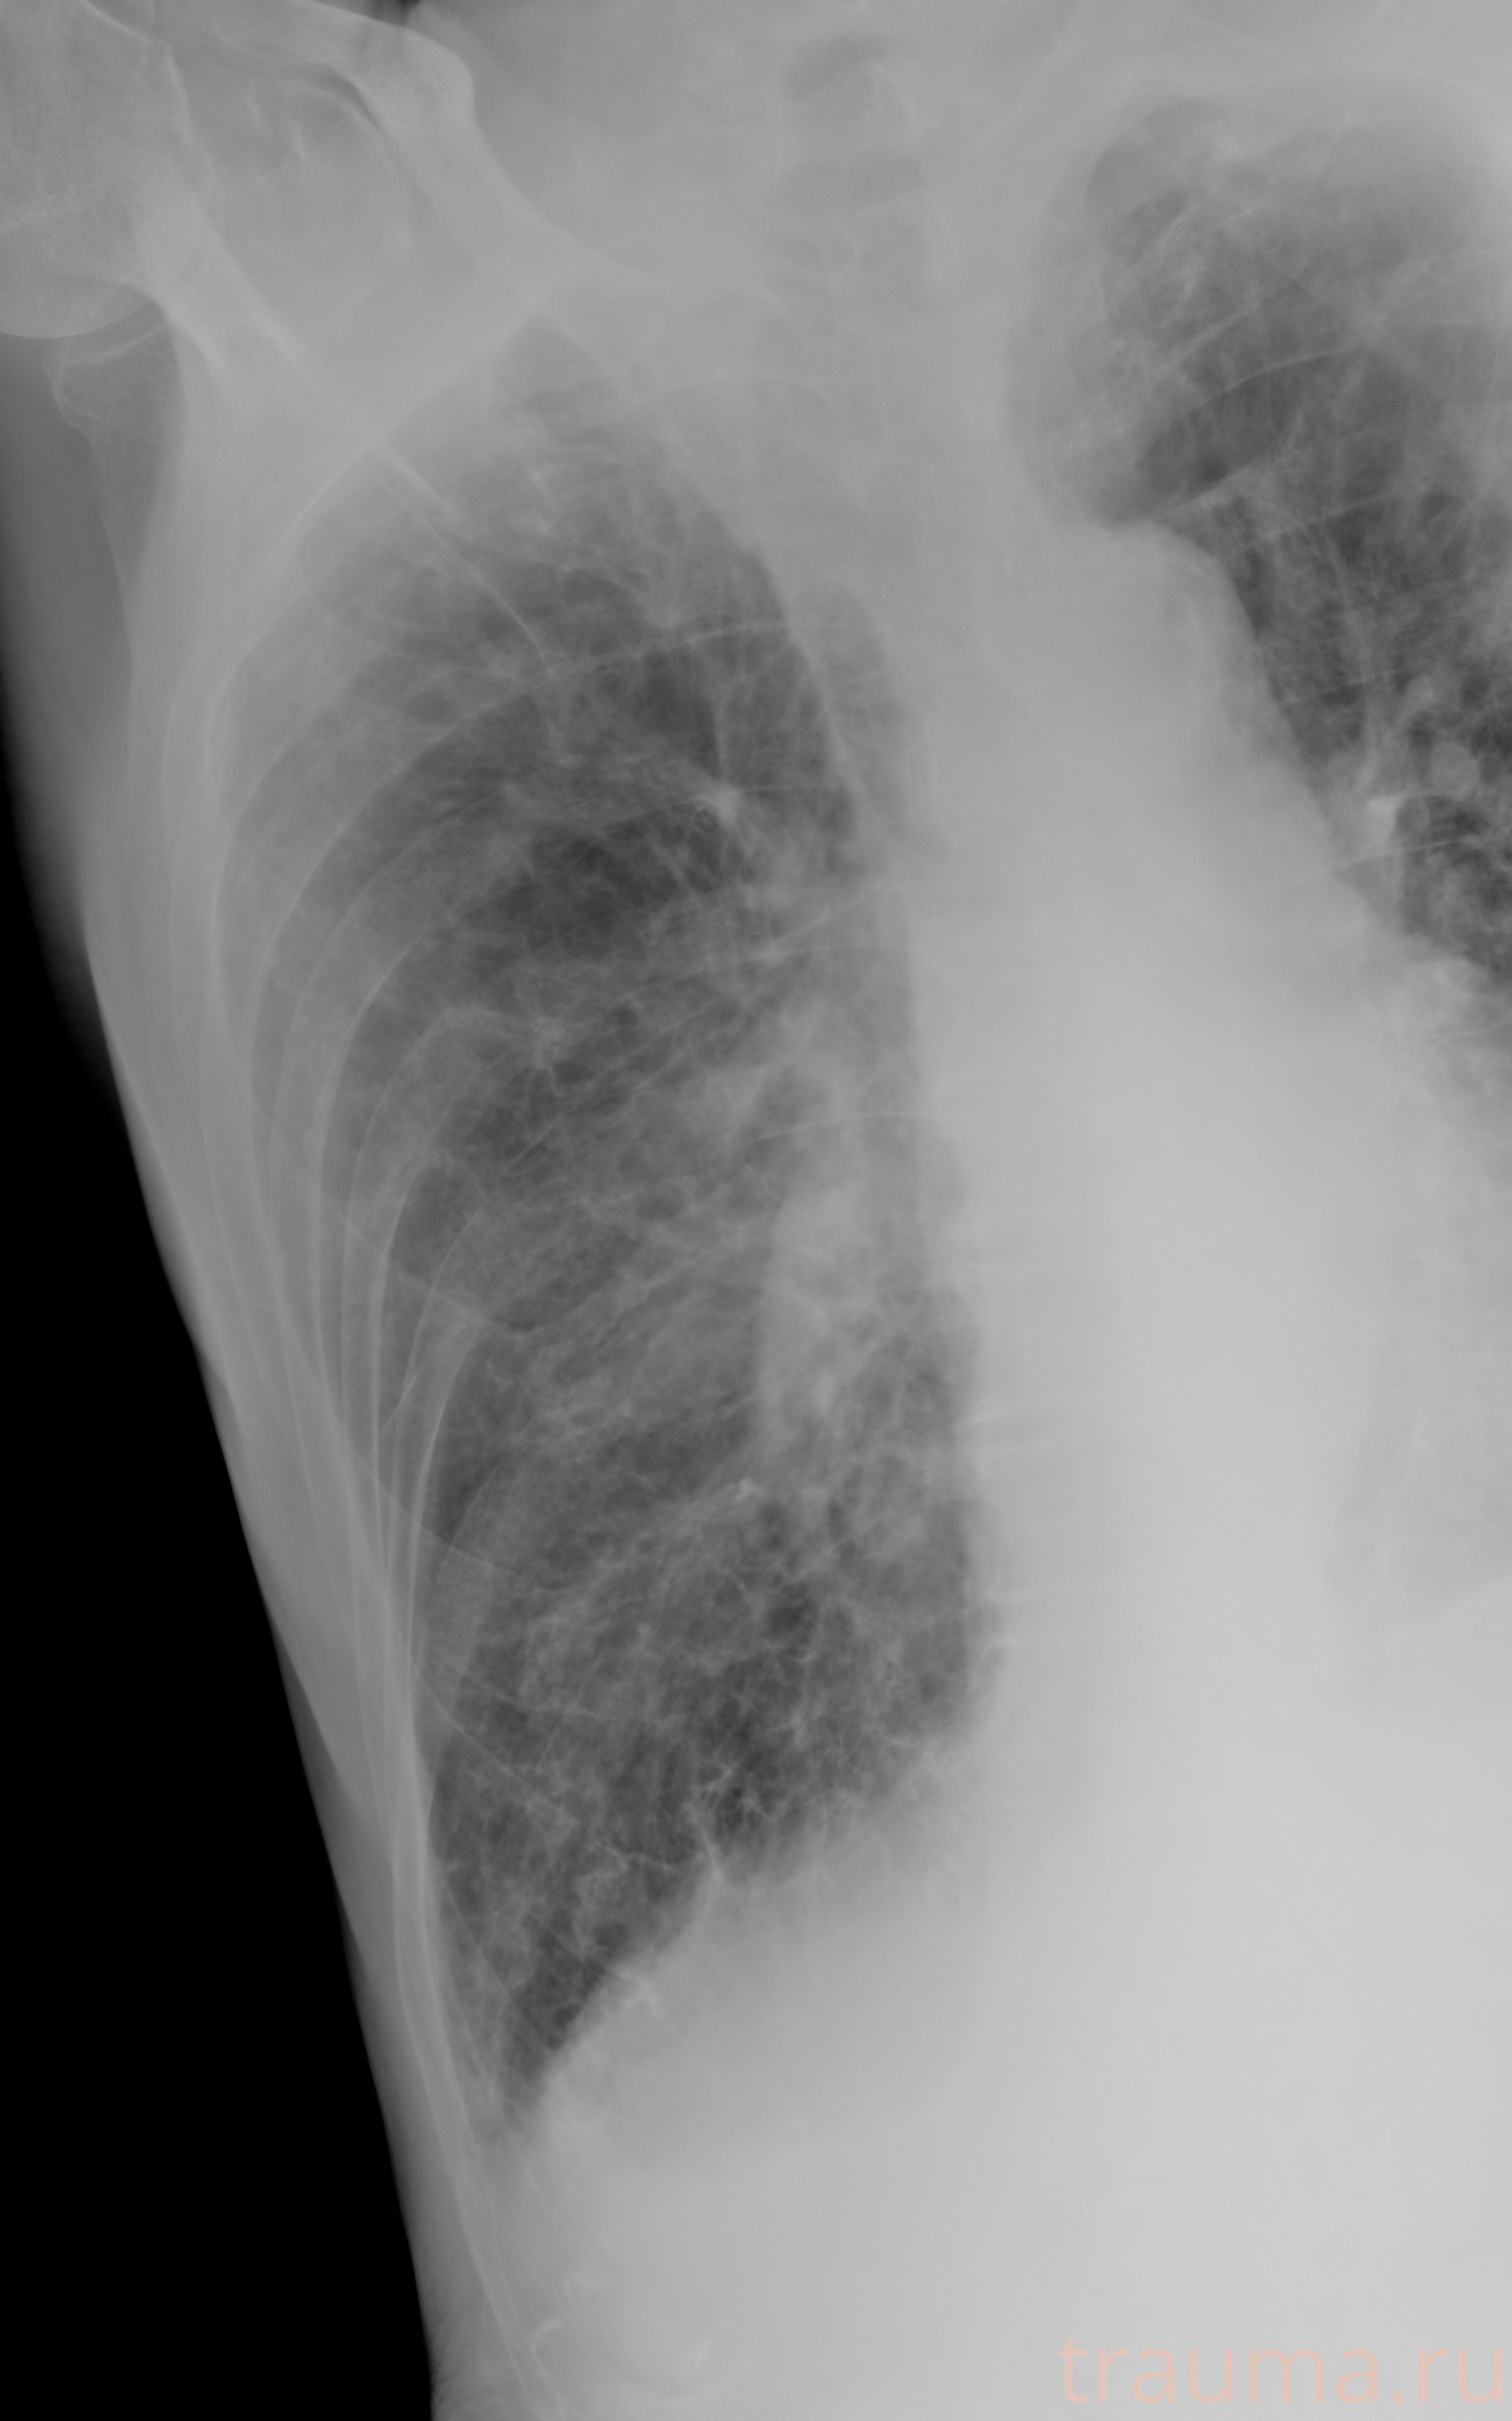

Рентген на дому: по вашему адресу приезжает врач-рентгенолог, травматолог-ортопед с мобильным рентгеновским аппаратом, проводит диагностику травмы или заболевания, делает необходимые рентгенограммы, дает рекомендации по дальнейшему лечению. Получить качественные снимки в домашних условиях возможно благодаря уникальной методике, разработанной МосРентген Центром для института  Склифосовского